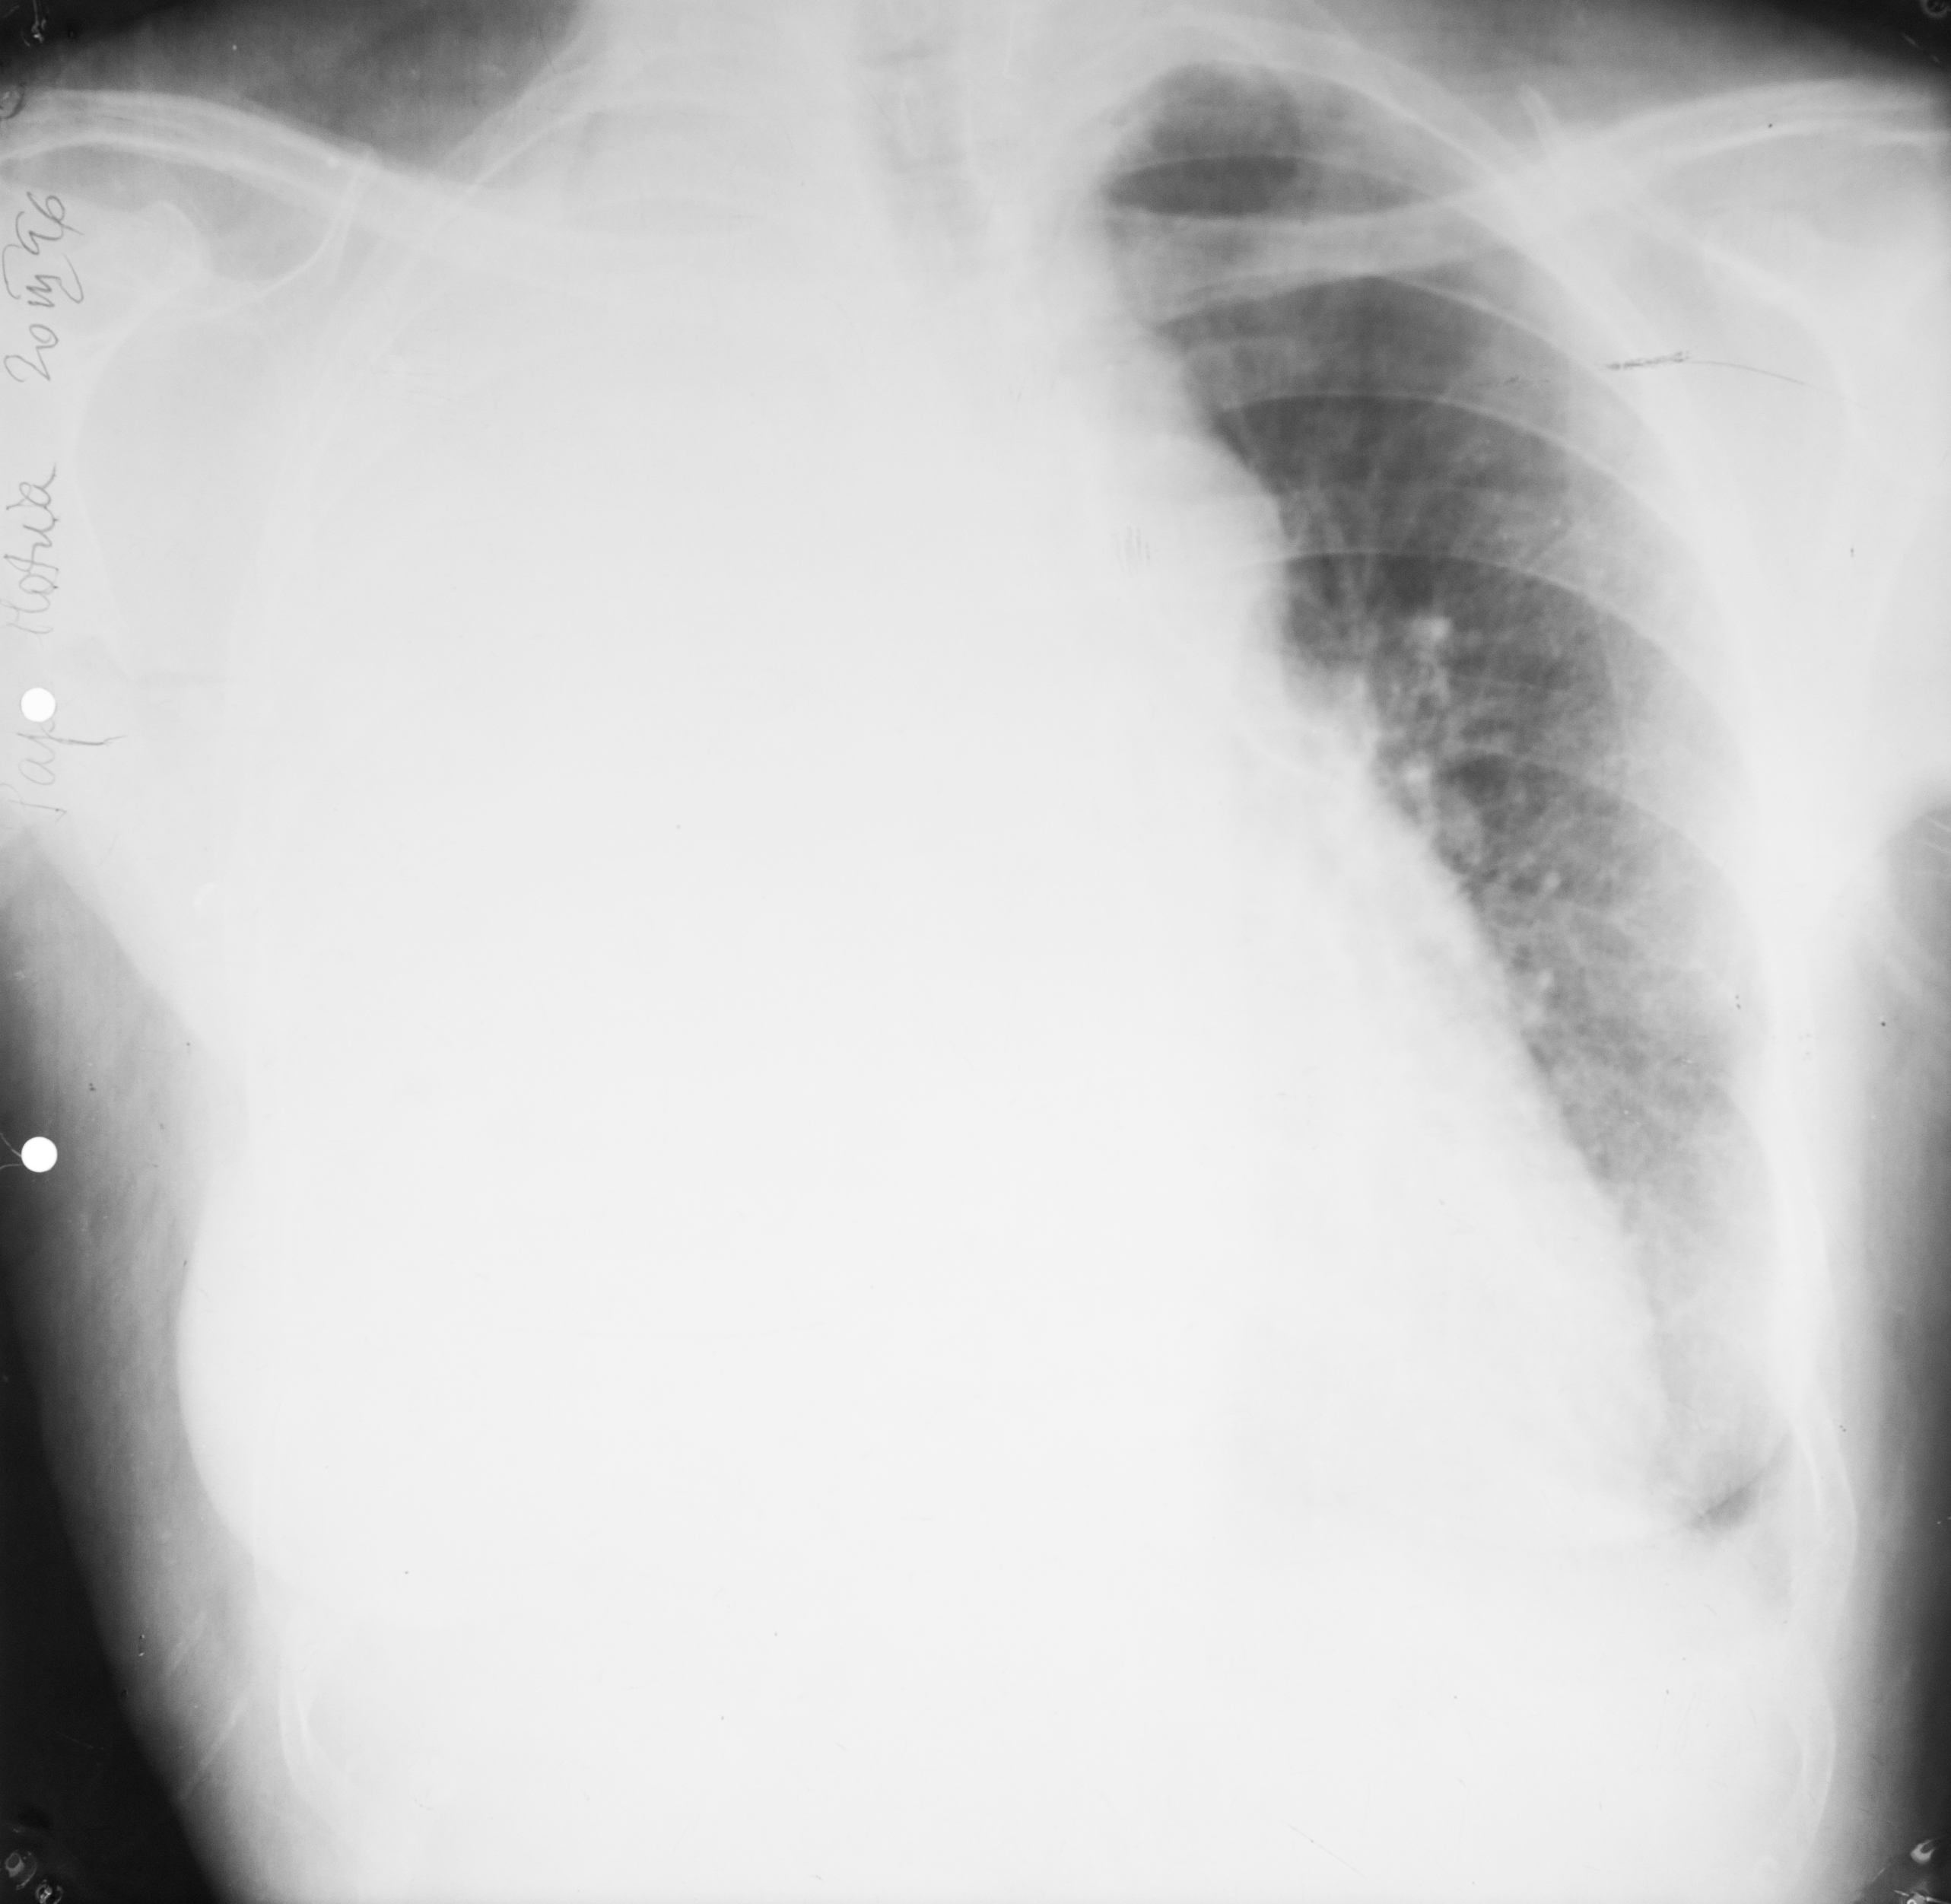

Opacifierea unui intreg camp pulmonar cu impingerea cordului si a mediastinului spre partea sanatoasa – colectie pleurala masiva

Opacifierea unui hemicamp pulmonar,de data aceasta cu tractionarea tuturor structurilor,a mediastinului si a hemidiafragmului – atelectazie